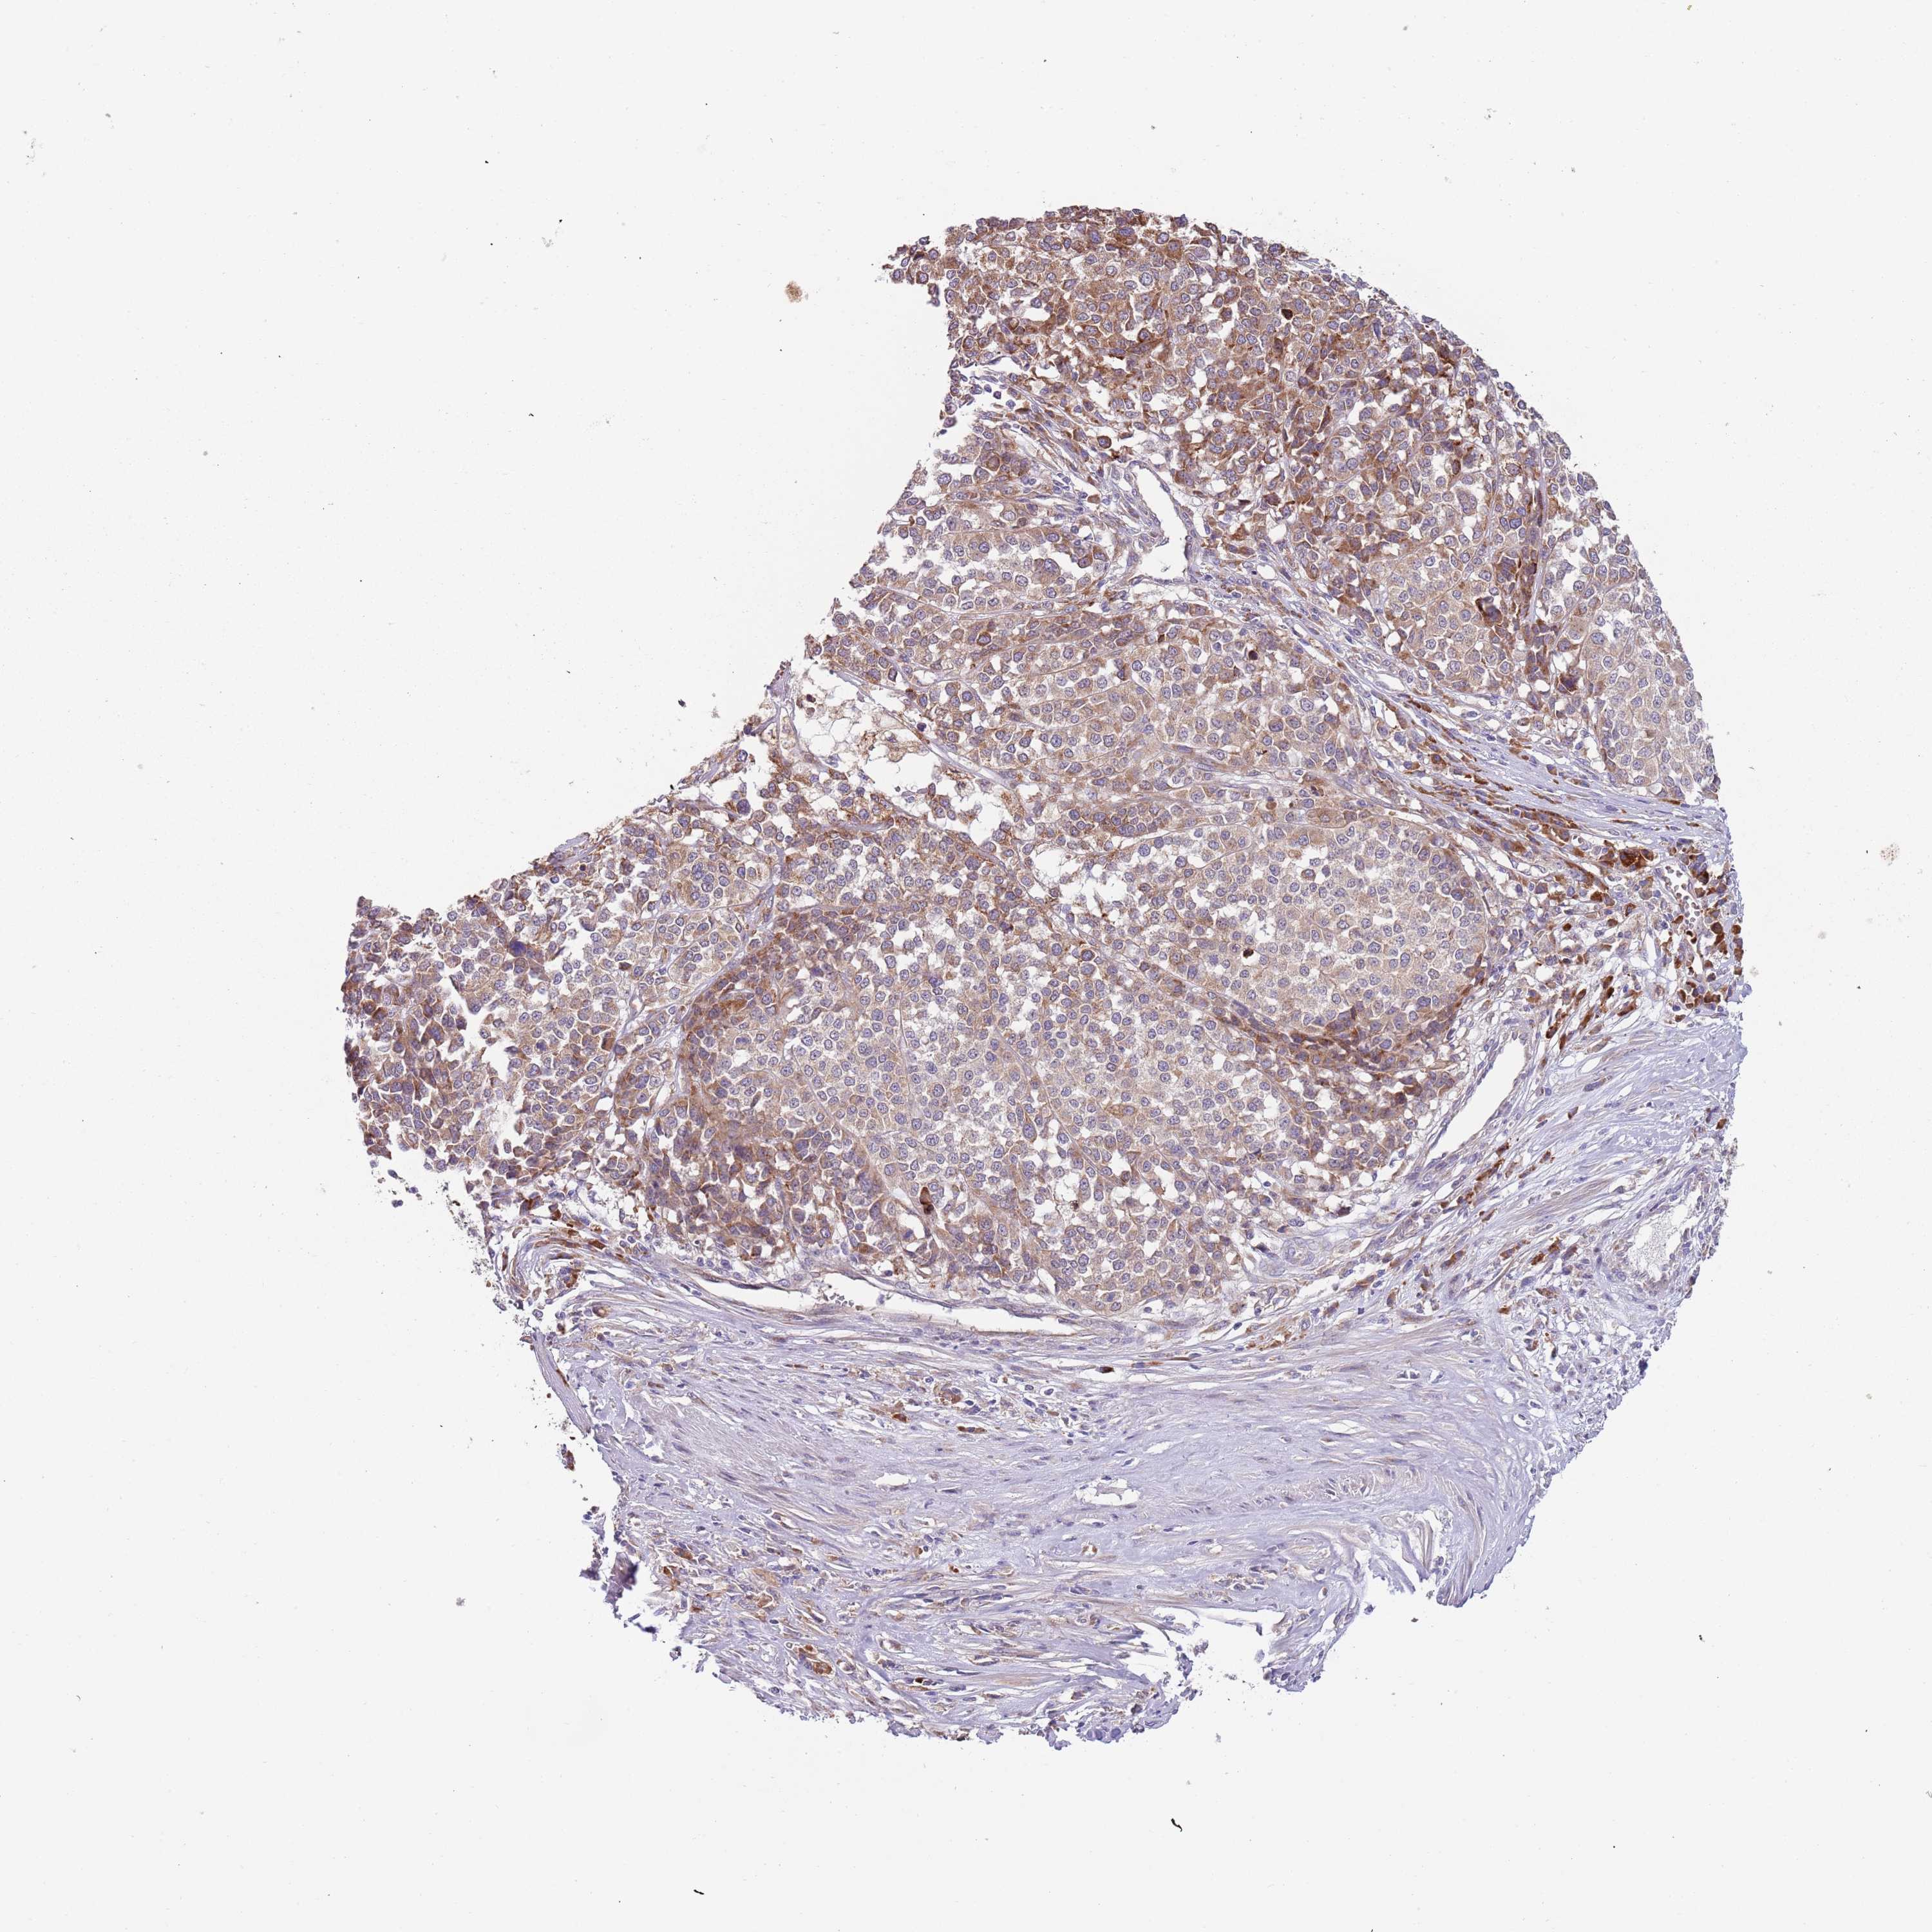

MELANOMA - Protein expressioni

A mouse-over function shows sample information and annotation data. Click on an image to view it in a full screen mode. Samples can be filtered based on level of antibody staining by selecting one or several of the following categories: high, medium, low and not detected. The assay and annotation is described here.

Note that samples used for immunohistochemistry by the Human Protein Atlas do not correspond to samples in the TCGA dataset.

Antibody stainingi

Antibody staining in the annotated cell types in the current human tissue is reported as not detected, low, medium, or high, based on conventional immunohistochemistry profiling in selected tissues. This score is based on the combination of the staining intensity and fraction of stained cells.

Each image is clickable and will lead to virtual microscopy that enables deeper exploration of all samples and also displays staining intensity scores, fraction scores and subcellular localization as well as patient and tissue information for each sample.

Antibody HPA040401

Antibody HPA043921

Staining

High

Medium

Low

Not detected

Intensity

Strong

Moderate

Weak

Negative

Quantity

>75%

75%-25%

<25%

None

Location

Nuclear

Cytoplasmic/membranous

Cytoplasmic/membranous,nuclear

Malignant melanoma, NOS

Malignant melanoma, Metastatic site